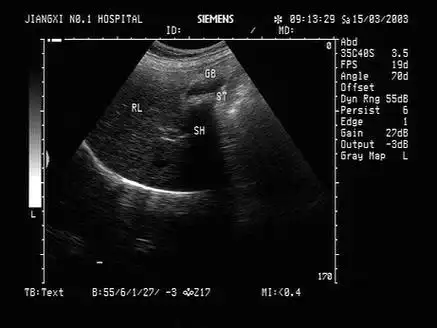

胆囊息肉多发性

b超"回声"大揭秘:胆结石是怎么被发现的?_超声_图像_反射

胆囊泥沙结石